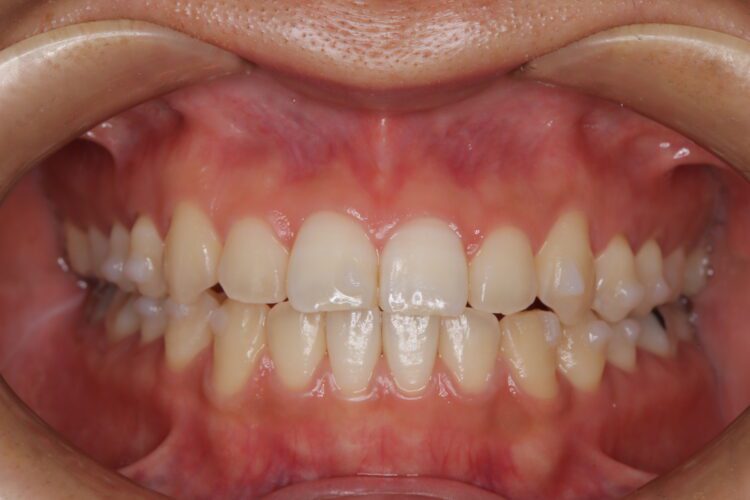

受け口の改善を主訴にご来院された患者様です。

軽度の下顎前突と診断し、マウスピース矯正装置(インビザライン)を用いて治療を行うこととしました。

治療の際はゴム掛けが必要になりましたが、患者様が非常に真面目に使用してくださったおかげで、スムーズに治療が進みました。途中の海外赴任という大きな予定変更がありましたが、そのご努力の甲斐あって、無事に渡航前に矯正を完了することができました。